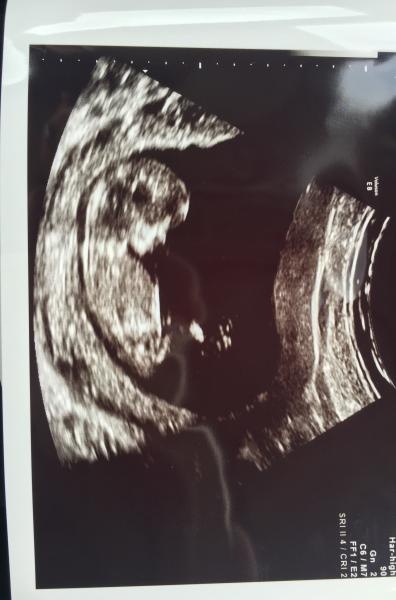

Var på kub idag och allt såg bra ut, 1:5059 för downs och 1:20000 för trisomi 13/18 :D

Den lille låg och sov så BM var såå nöjd och kunde mäta noggrant. Sen fick jag hosta och skratta lite för att väcka den lille. BM vågade gissa på kön och tittade lite extra noga och var rätt säker på en liten pojke! Vi fick med oss 10st bilder hem i alla möjliga vinklar. Så lyckliga över en fin dag och glada besked!